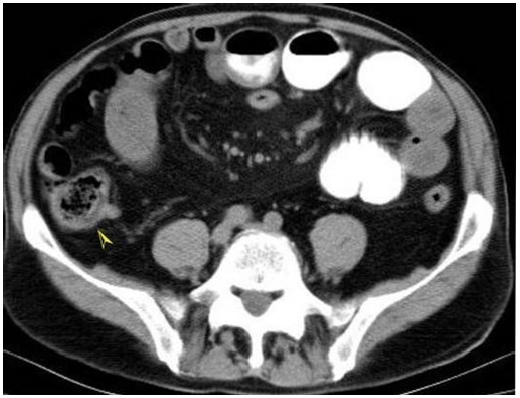

A forty-four-year-old male patient was admitted, for three days of epigastric pain, nausea, and vomiting. In his clinical history, it was learned that 3 days ago, he was examined in another center where he applied with his current complaints and, hospitalization was recommended, and the patient did not accept. Despite the improvement of her vomiting complaint, he re- applied to the hospital because of her epigastric pain did not decrease. There was no known comorbid disease history and no previous abdominal surgery intervention. In the physical examination at admission, there was epigastric tenderness, but no defense or rebound existed. In laboratory examinations, no pathology was detected except leukocytosis (15100/mm3), high amylase and lipase (747 IU/L and 1202 IU/L) levels. Abdominal ultrasonography examination (USG) revealed that; the pancreas was evaluated as having minimal edema, gallbladder wall and lumen content were normal. Abdominal computed tomography (CT) examination revealed that; peripancreatic minimal edema and inflammation observed, which was suggestive of acute pancreatitis. The gallbladder was normal. Also, a phytobezoar detected in the ileum lumen that was roundshaped, 2x2 cm in diameter, with an air bubble appearance and not causing intestinal obstruction (Figure 1).

Figure 1: Abdominal CT; phytobezoar appearance in the ileum lumen which has round shape, 2x2cm in diameter and air bubble appearance into it (arrow head).